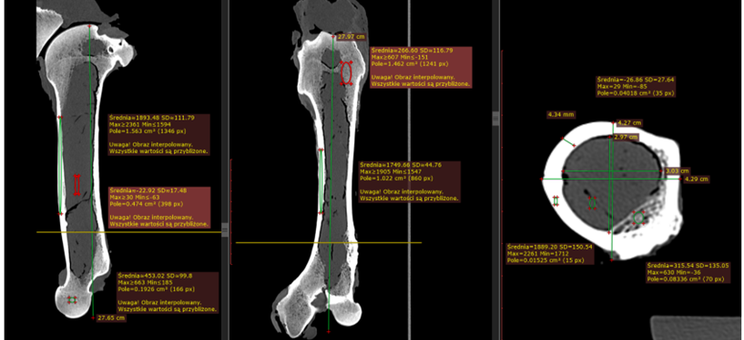

Korelacja wyników Ilościowej tomografii komputerowej (QCT) gęstości mineralnej kości zapisanych w skali Haunsfielda z modułem Younga będącym jednym z głównych parametrów opisujące własności mechaniczne kości.

Pomiary modułu Younga wykonane zostały za pomocą dwóch metod: maszyny wytrzymałościowej INSTRON oraz za pomocą metody bazującej na dyfrakcji światła. Pomiaru gęstości mineralnej kości dokonano za pomocą tomografu komputerowego z wzorcowym fantomem gęstości kości.